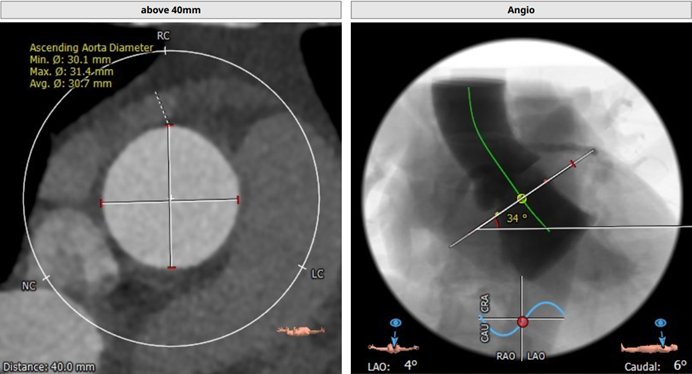

术前CT分析

瓣环

周长:68.1mm 平均直径:21.7mm

法氏窦

直径:25.3*24.2*25.1mm

窦管结合部

平均直径:25.8mm

升主动脉

平均直径:31.9mm

左冠高度高度:14.6mm

右冠高度高度:9.8mm

主动脉瓣角度 44°

钙化积分68mm³

左冠瓣叶长度:19.2 mm,右冠瓣叶长度:17.4 mm

瓣环平均直径:26.0 mm,左室流出道平均直径:28.1 mm

升主动脉未见明显扩张,心脏角度:34°

左冠开口高度:16.4 mm;右冠开口高度:15.6 mm